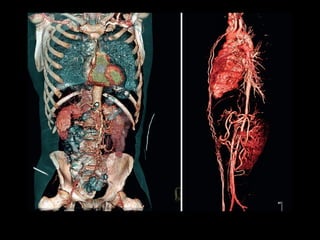

TOMOGRAFIA COMPUTADORIZADA